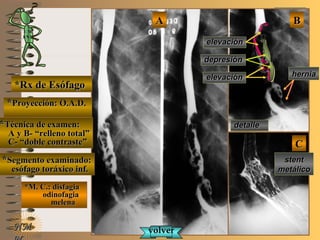

*Rx de Esófago*Rx de Esófago

**Proyección:Proyección:

**Técnica de examen:Técnica de examen:

A y B-A y B-

C-C-

**Segmento examinado:Segmento examinado:

*M. C.: disfagia*M. C.: disfagia

odinofagiaodinofagia

melenamelena

NMNM

O.A.D.O.A.D.

““relleno total”relleno total”

““doble contraste”doble contraste”

esófago toráxico inf.esófago toráxico inf.

A-A-El examen es normal o patológico?El examen es normal o patológico?

Examen patológico de esófago toráxico con téc-Examen patológico de esófago toráxico con téc-

nica en A y B- relleno total y C- doble contrastenica en A y B- relleno total y C- doble contraste

en proyección O.A.D.en proyección O.A.D.

B-B-La patología es congénita o adquirida?La patología es congénita o adquirida?

Patología adquiridaPatología adquirida

D-D-La misma es neoplásica o no neoplásica?La misma es neoplásica o no neoplásica?

Patología adquirida orgánica neoplásicaPatología adquirida orgánica neoplásica

E-E-Puede describir la o las imágenes patológicas?Puede describir la o las imágenes patológicas?

Se identifica en el tercio inferior de esófago torá-Se identifica en el tercio inferior de esófago torá-

xico una imagen elevado-deprimida, de bordesxico una imagen elevado-deprimida, de bordes

irregulares, relleno heterogéneo, compatibleirregulares, relleno heterogéneo, compatible

con C.A. avanzado tipo II decon C.A. avanzado tipo II de BorrmannBorrmann UNTUNT

asociado a hernia hiatal; control de ubicaciónasociado a hernia hiatal; control de ubicación

de stent paliativo para permeabilizar la luzde stent paliativo para permeabilizar la luz

C-C-Dicha patología es orgánica, funcional o mixta?Dicha patología es orgánica, funcional o mixta?

Patología adquirida orgánicaPatología adquirida orgánica

**Proyección: O.A.D.Proyección: O.A.D.

A y B- “relleno total”A y B- “relleno total”

C- “doble contraste”C- “doble contraste”

BBAA

CC

detalledetalle

depresióndepresión

elevaciónelevación

herniahernia

stentstent

metálicometálico